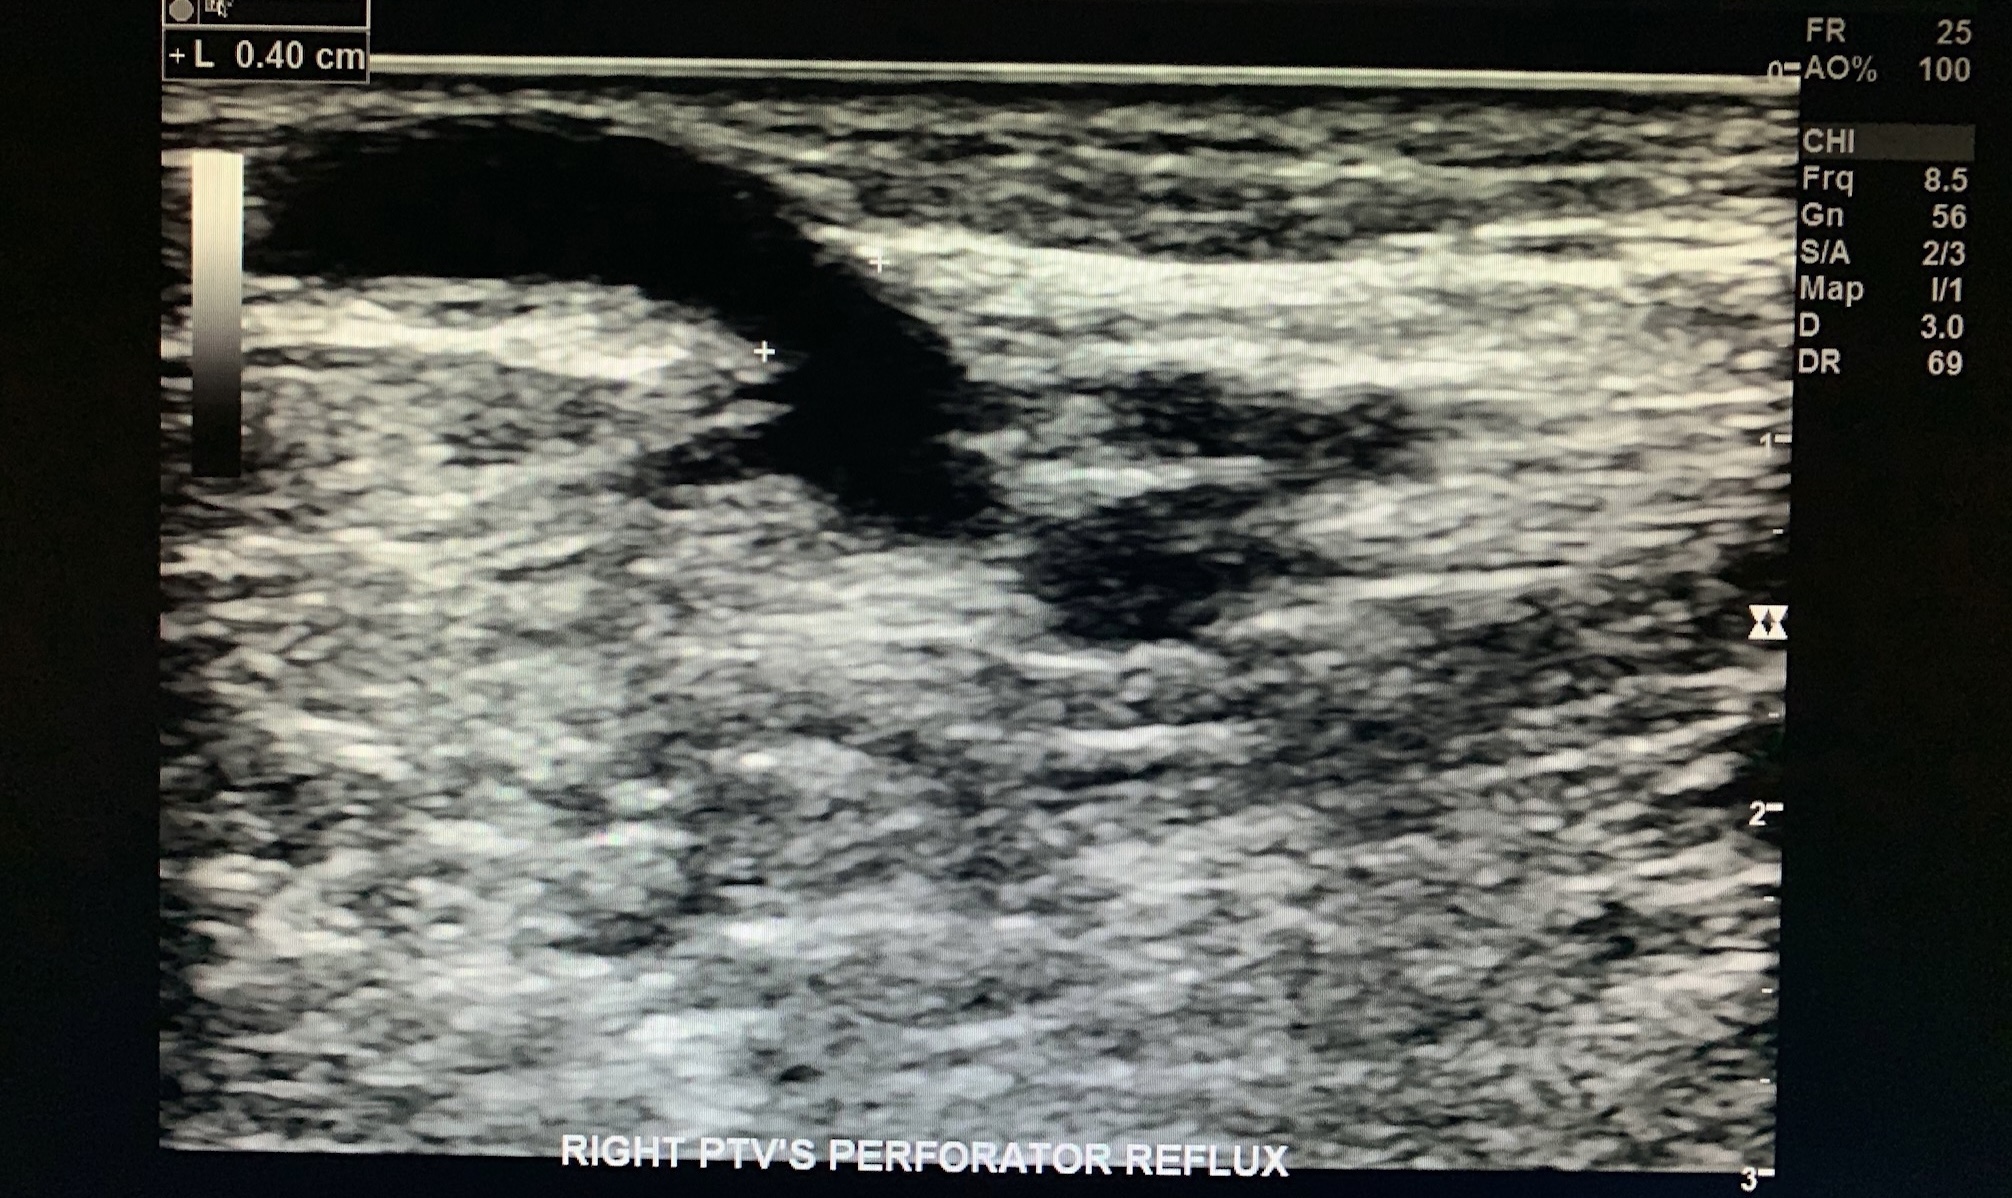

Measure the wall diameter (varicose >3mm) of the incompetent perforator vein.

Tibial vein perforator